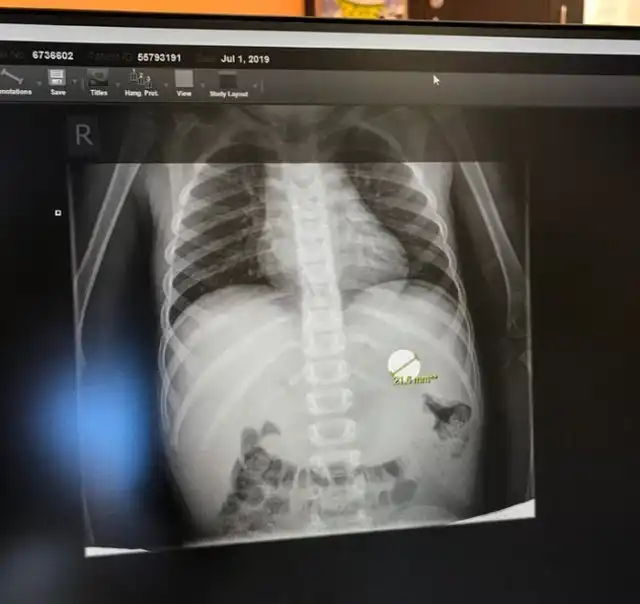

"Мой племянник съел монету"